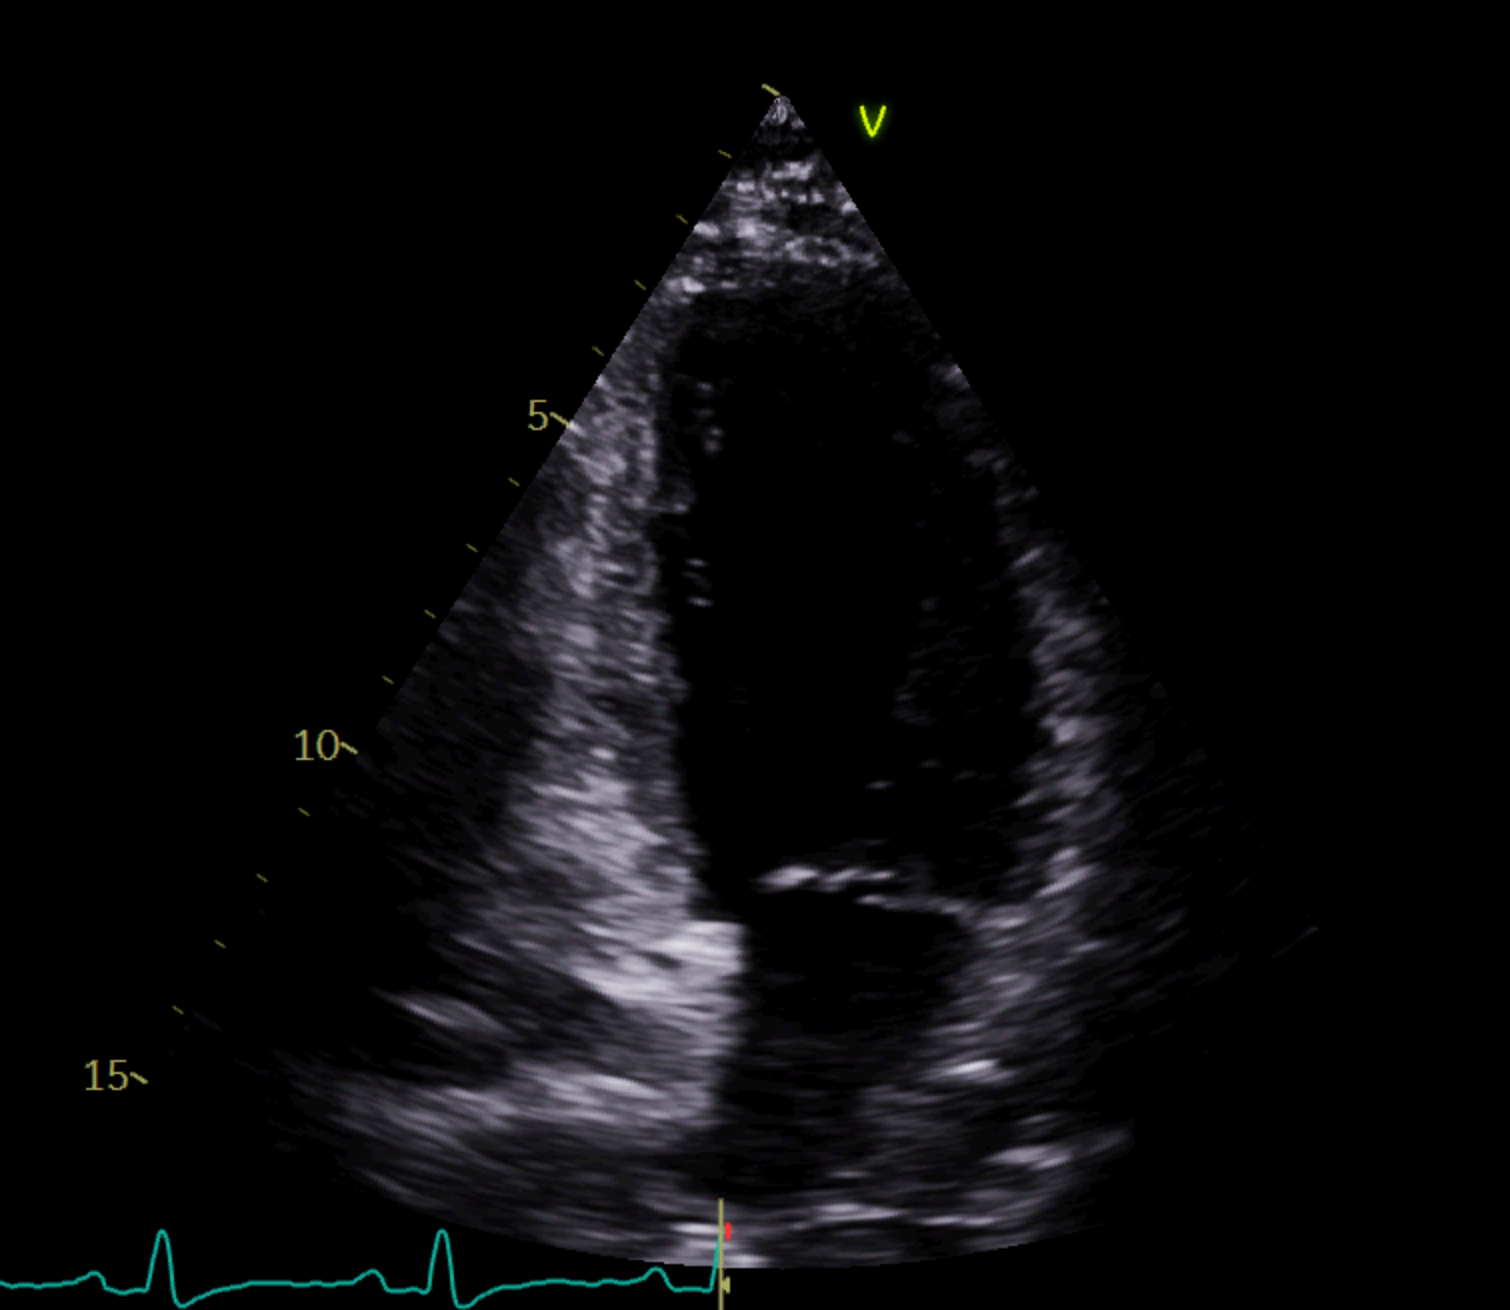

Ecografía a pie de calle: hipercontractilidad de bases e hipocinesia de segmentos medio-apicales. Fracción de eyección del ventrículo izquierdo conservada. Sin derrame pericárdico. Impresiona engrosamiento de pared libre de ventrículo derecho.

Posteriormente durante su ingreso perdura nuevo episodio de dolor torácico y se determina Troponina en pico de 5.989 ng/L. Se realiza ecografía y ventriculograma que sugieren STT. A consecuencia de esto, la estenosis de la DA supondría un hallazgo y no la causa principal del dolor torácico.